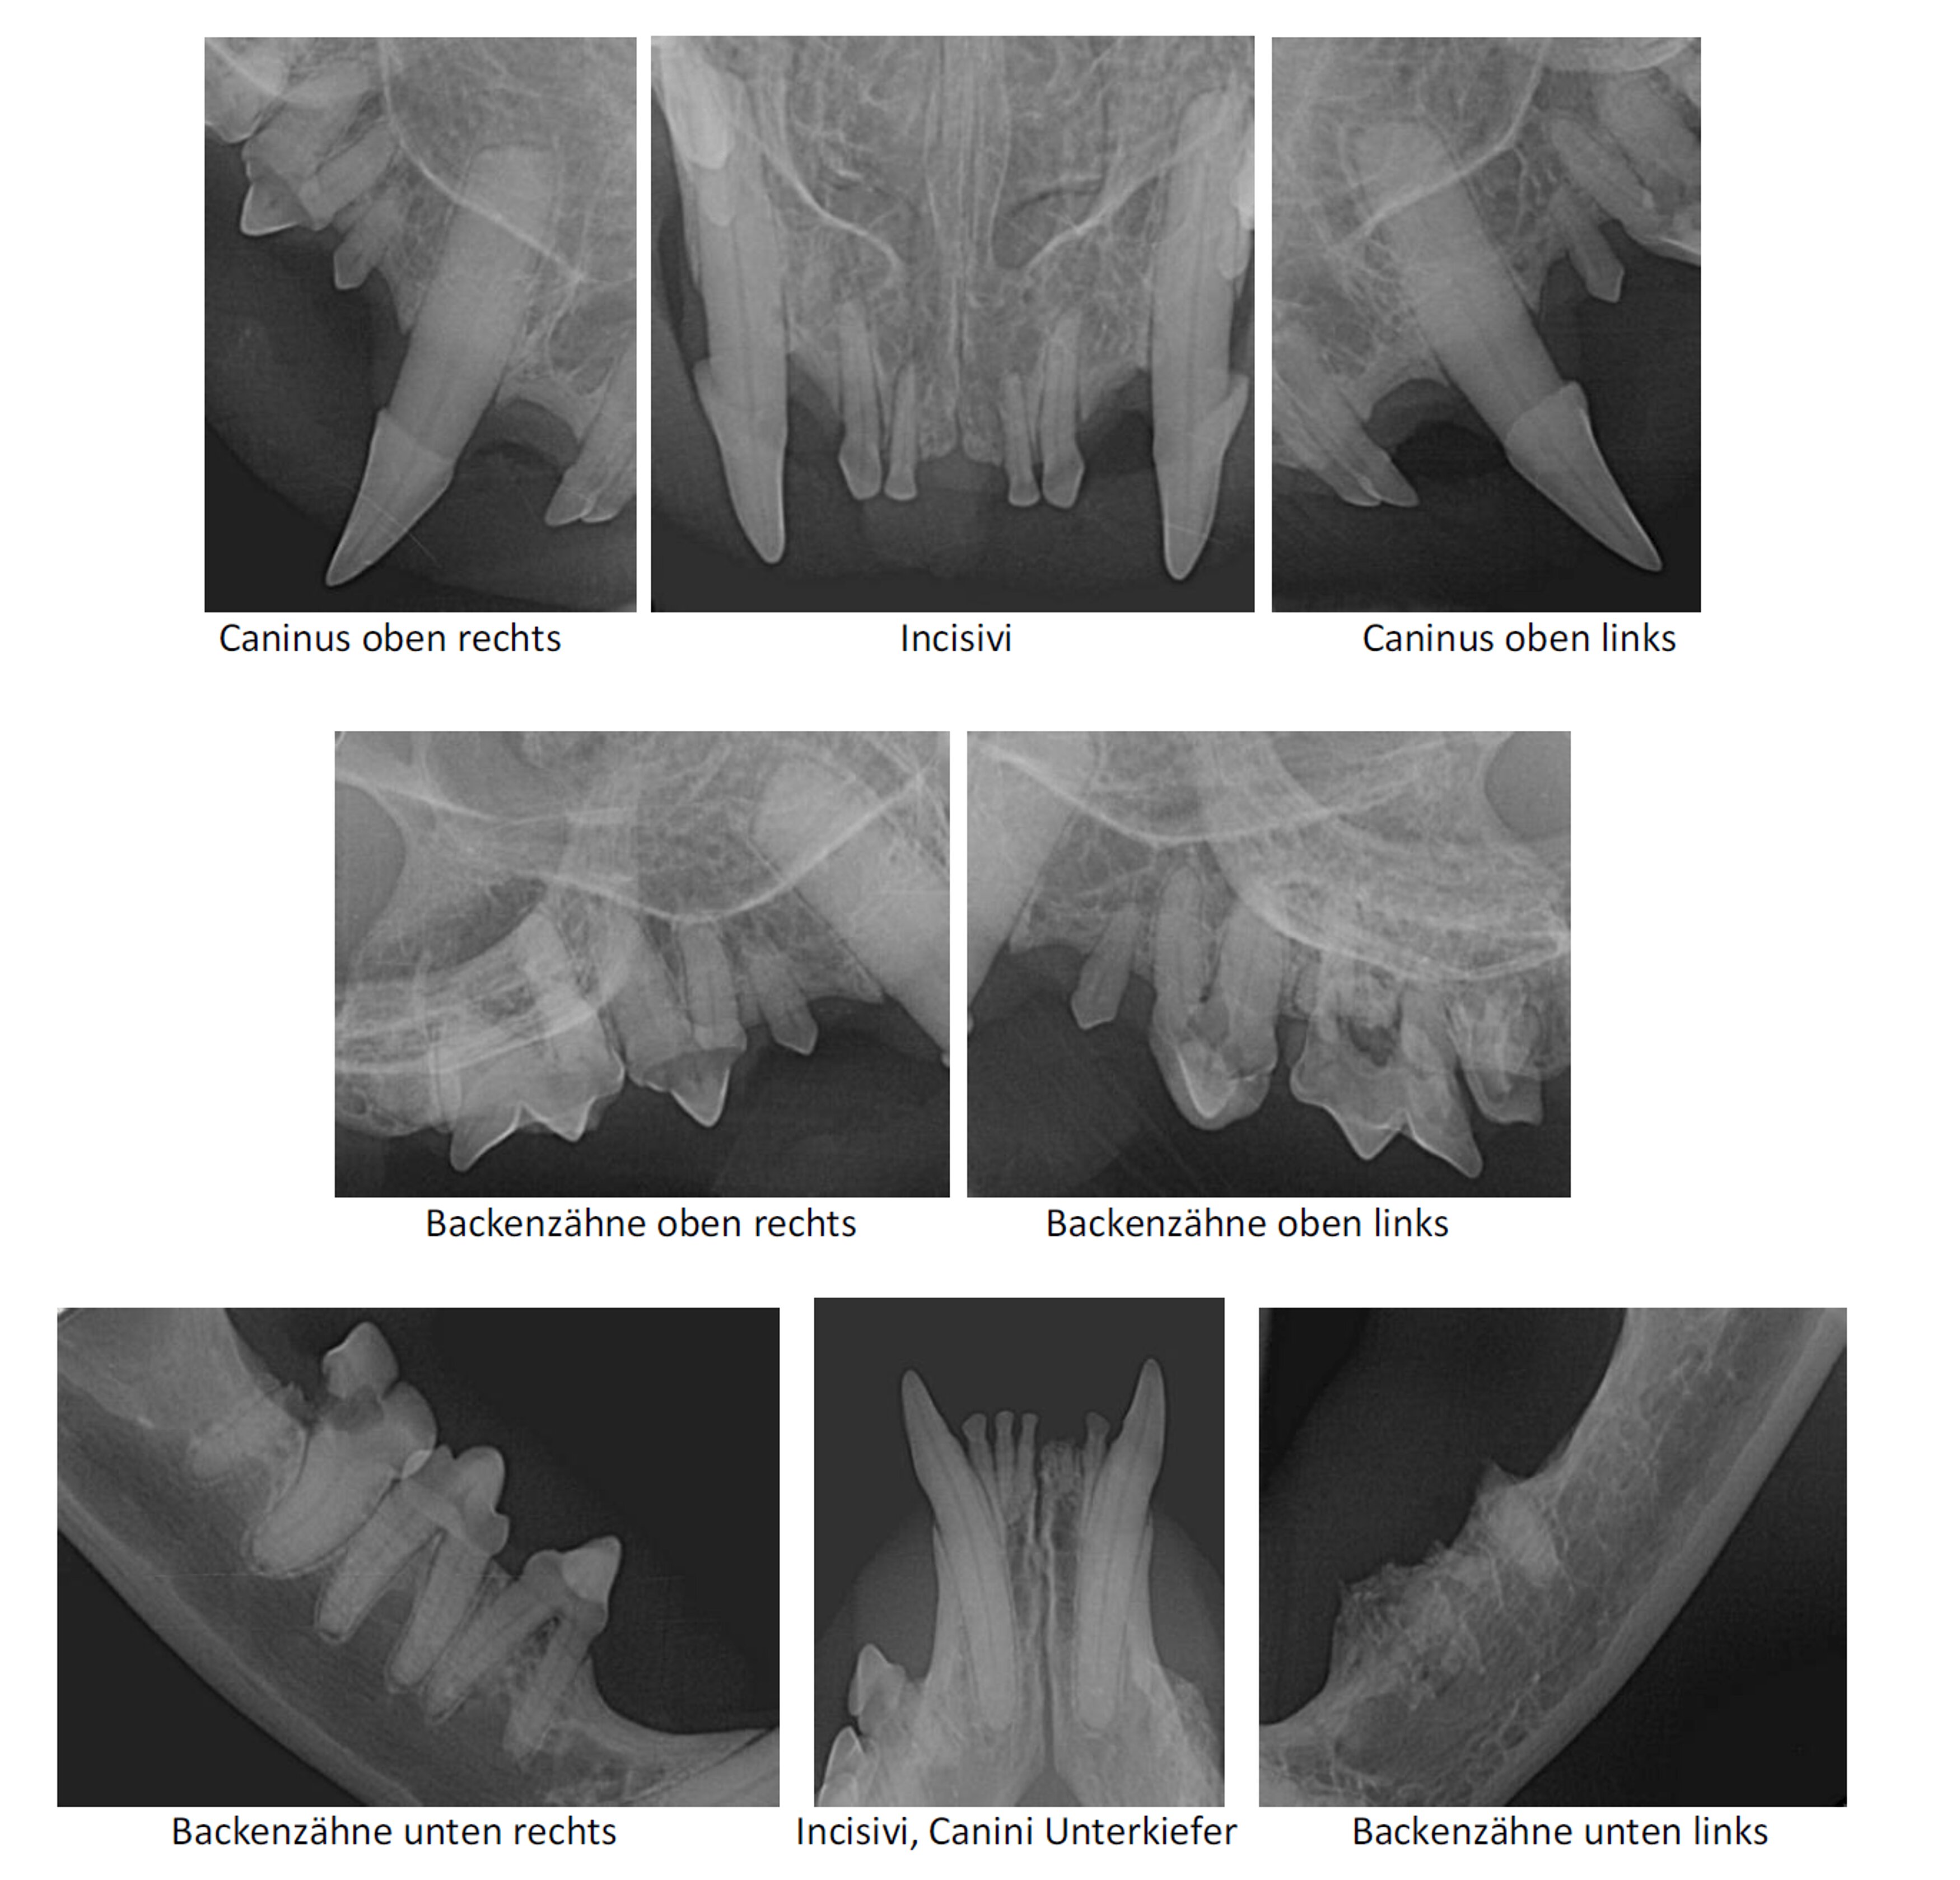

Ist ein Zahnröntgen unbedingt erforderlich?

Ja, denn wie bei einem Eisberg, dessen größter Teil sich unter Wasser befindet, liegt ein Großteil jedes Zahnes unter dem Zahnfleisch im Knochen verborgen. Ohne Zahnröntgen werden deshalb 30 bis 40 Prozent der Erkrankungen der Wurzeln eines Zahnes sowie Veränderungen des Zahnhalteapparates oder des Knochens übersehen. Aus diesem Grund sollten bei jeder professionellen Zahnreinigung Röntgenaufnahmen von allen Zähnen angefertigt werden.